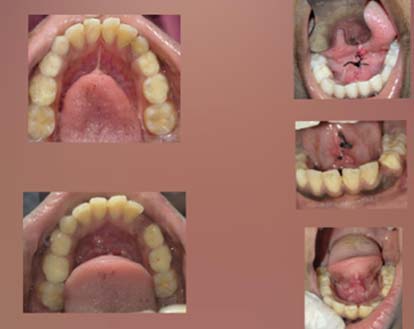

While some tongue ties are easy to diagnose, others can be much more difficult. Most commonly, babies have an anterior tongue tie � which is a tongue tie at the front of the mouth.

Some, however, have a posterior tongue tie, at the back of the mouth, which is much harder to spot. This is often called a �hidden tongue tie�. Sometimes posterior tongue ties are not even visible when the whole tongueue is lifted, but they do have an effect on baby�s tongue movement.